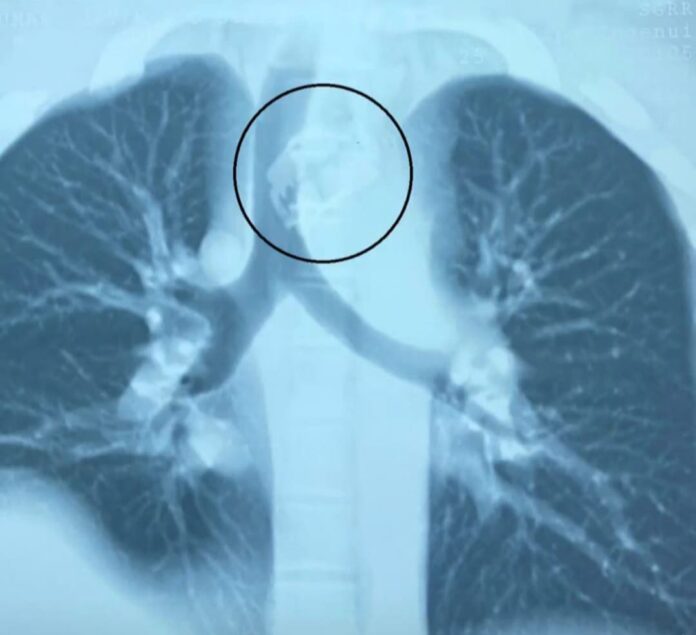

श्री महंत इन्दिरेश अस्पताल के नाक कान गला रोग विभाग के डाॅक्टरों ने प्रारम्भिक जाॅचां मे पाया कि ब्लेड श्वास नली के निकट महत्वपूर्ण खून की सबसे बड़ी नस के काफी नजदीक अटकी हुई है।

श्री महंत इन्दिरेश अस्पताल के असिस्टेंट प्रोफेसर व ईएनटी सर्जन डॉक्टर शरद हरनोट ने सीनियर रेजिडेंट डॉ. फातमा अंजुम के साथ मरीज की सफल सर्जरी की और एंडोस्कोपी द्वारा पूर्ण रेजर ब्लेड को खाने की नली से बाहर निकाला।

मरीज के पिता ने जानकारी दी कि अज्ञात परिस्थिति में मरीज ने रेजर ब्लेड को निगल लिया। उन्होंने बताया कि वो उत्तराखण्ड के कई अन्य बड़े अस्पतालों में उपचार के लिए गए लेकिन मरीज की समस्या का समाधान नहीं हुआ और रेफर कर दिया गया। इसके बाद वह अपने पुत्र को लेकर श्री महंत इन्दिरेश अस्पताल आए। श्री महंत इन्दिरेश अस्पताल के असिस्टेंट प्रोफेसर व ईएनटी सर्जन डॉक्टर शरद हरनोट ने सीनियर रेजिडेंट डॉ. फातमा अंजुम के साथ मरीज की सफल सर्जरी की और एंडोस्कोपी द्वारा पूर्ण रेजर ब्लेड को खाने की नली से बाहर निकाला।